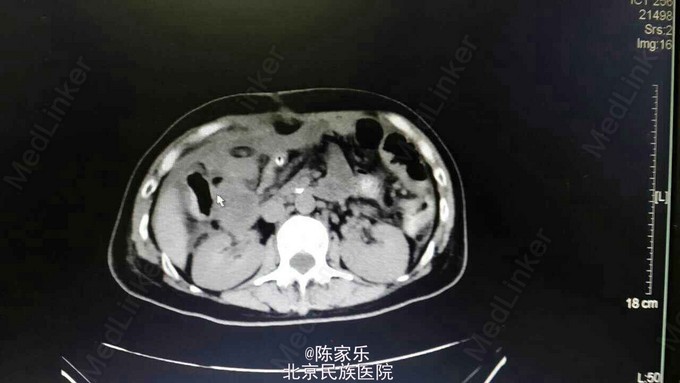

主诉:上腹部疼痛伴呕血2小时 现病史:女,55岁,2小时前无明显诱因突发上腹部疼痛,疼痛无向他处放射,伴恶心、呕暗红色血,量血100ml,无腹胀、腹泻、头晕、心季等不适。 既往史:1个月前因胰头癌行胰十二指肠切除术。否认高血压、糖尿病、肝炎、胃溃疡病史。

查体:腹部平软,上腹部轻压痛,无肌紧张、反跳痛。 实验室检查:未见明显异常 CT:胰十二指肠切除术后改变,肝门区及肝周积液,肝右叶近包膜区低密度灶,肝内胆管轻度扩张。